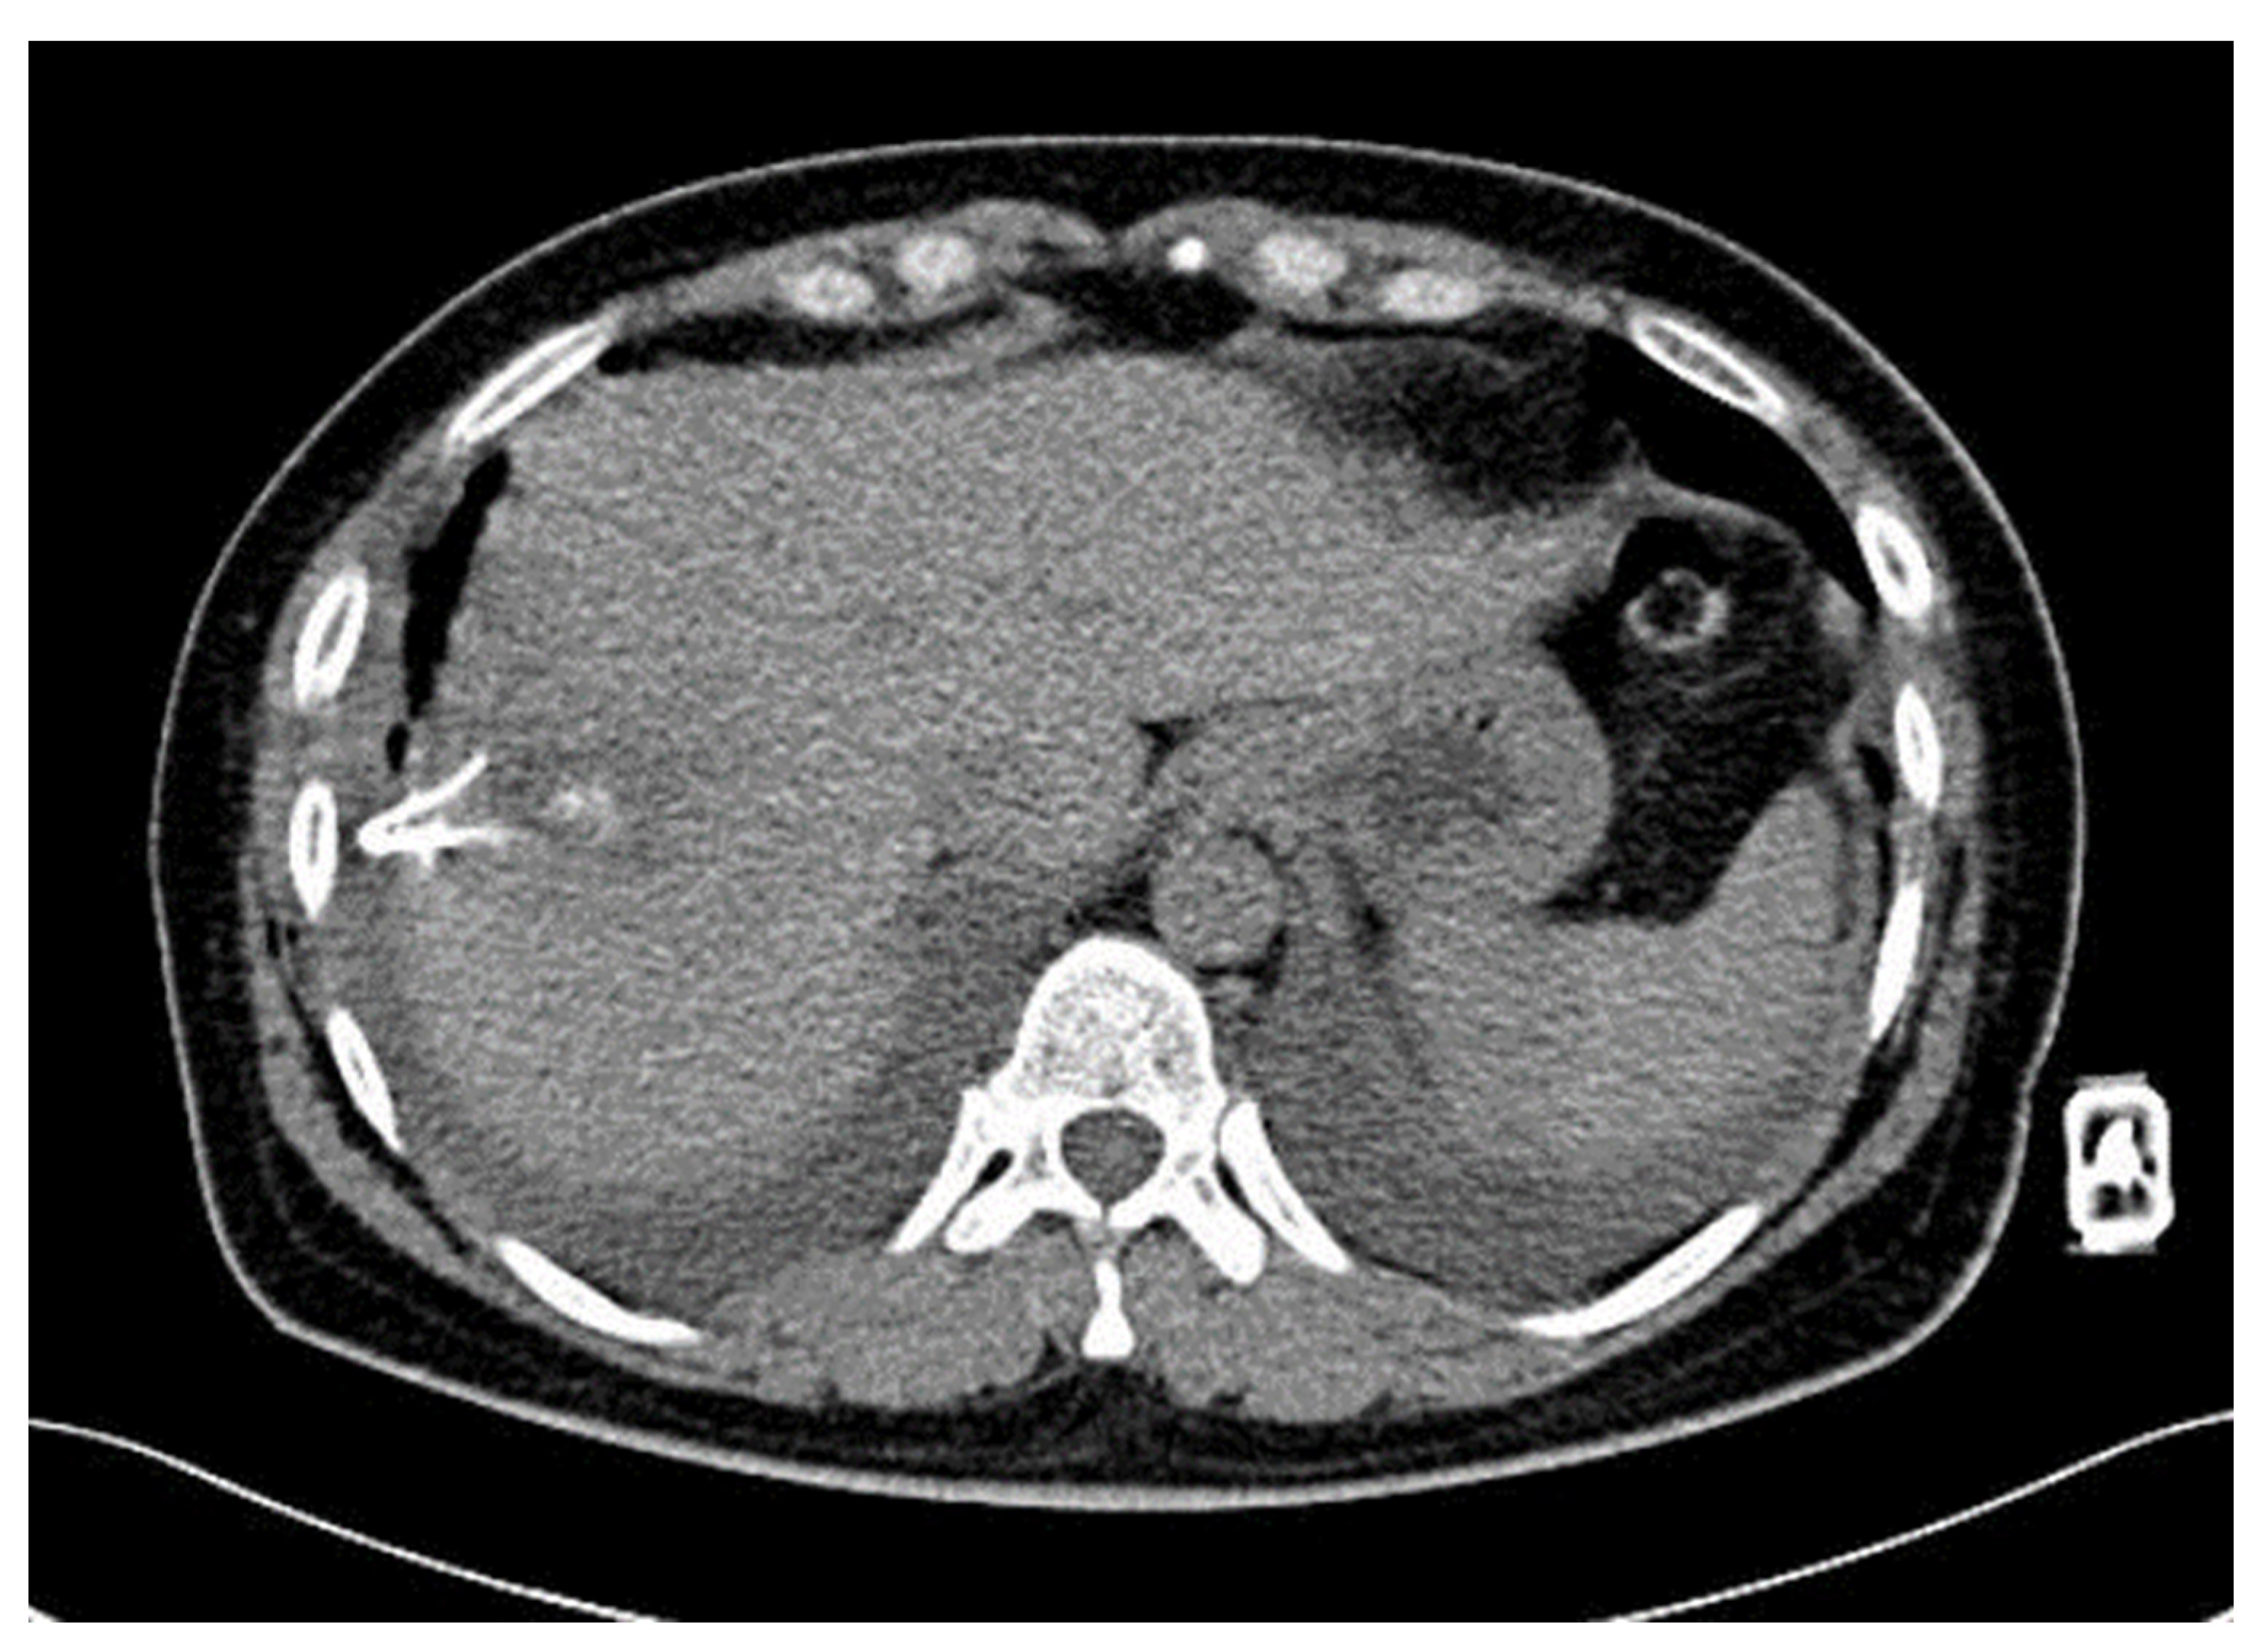

Diaphragmatic Liver Herniation after Radiofrequency Ablation of a Secondary Liver Tumor

Hoskovec, D.; Hořejš, J.; Krška, Z.; Argalácsová, S.; Klobušický, P. Diaphragmatic Liver Herniation after Radiofrequency Ablation of a Secondary Liver Tumor. Diagnostics 2024, 14, 26. https://doi.org/10.3390/diagnostics14010026